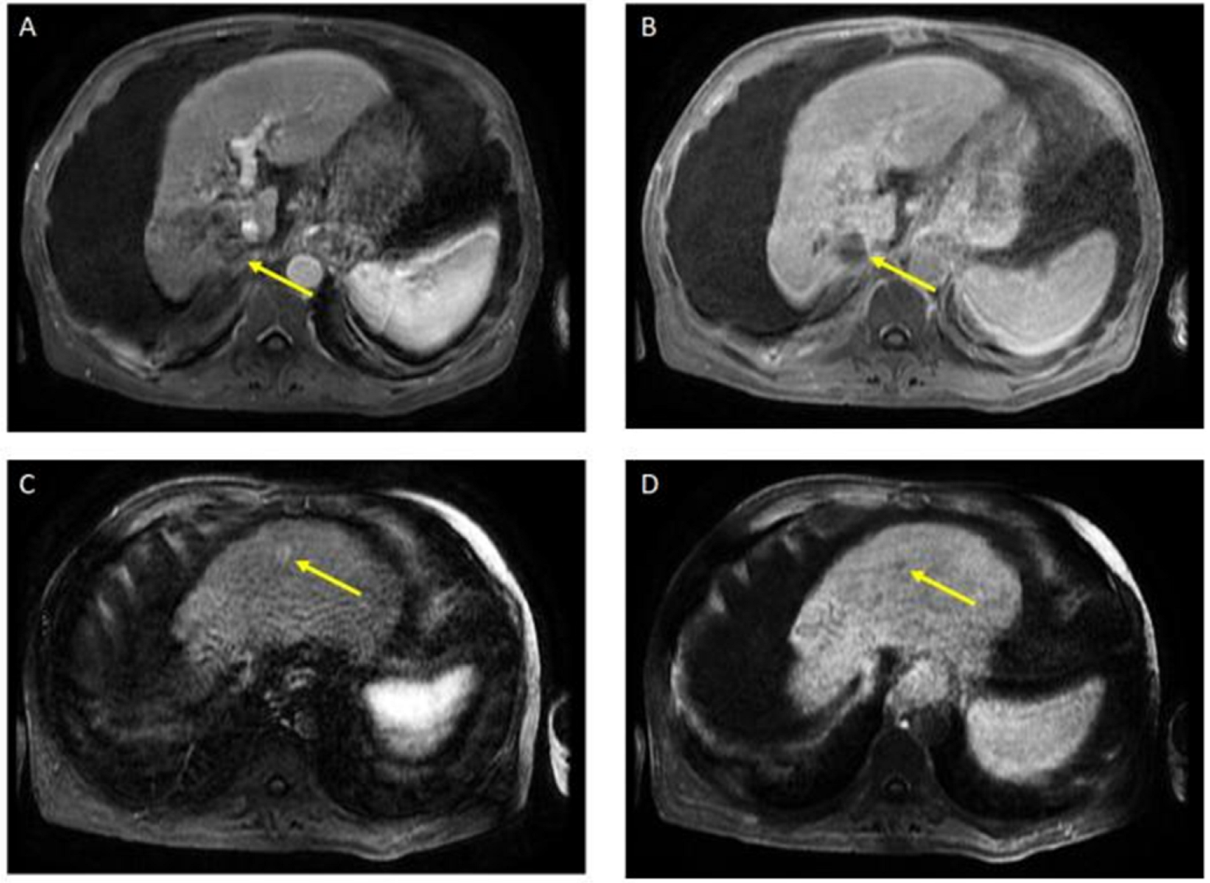

The patient received a total of 6 cycles of atezolizumab 1200 mg intravenously plus a total of 5 cycles of bevacizumab 15 mg/kg (missed one cycle of bevacizumab) given on day 1 of a 21-day cycle. Therapy was then held for two months prior to evaluation for OLT. Follow-up MRI 8 weeks after treatment showed a significant interval treatment response with shrinkage of the segment 7 tumor, as seen in Figure 2. Additional imaging follow-up at 6 months showed post-treatment atrophy of the right lobe of the liver, stable non-enhancing segment 7 mass (LR-TR non-viable); with a new 8 mm lesion in segment 2 of the liver (LI-RADS 4 for arterial enhancement, washout, and size less than 10 mm), as can be seen in Figure 3. PET/CT scan showed no metabolic uptake in the right hepatic lobe with suspected inflammatory uptake in the common bile duct. No bone metastases were appreciated in the bone scan.

Figure 3.

Magnetic resonance imaging of the abdomen. Post-treatment atrophy of the right hepatic lobe, cirrhosis, splenomegaly, and ascites were noted. T1 post-contrast early (A) and delayed (B) demonstrate phase unchanged Seg 7 non-enhancing 4.5 cm cavity (LR TR nonviable); T1 with contrast early (C) and delayed (D) show new 8 mm lesion in segment 2 with early enhancement and late washout (LR 4) (captured at the follow-up visit, and 6 months after the atezolizumab plus bevacizumab started).